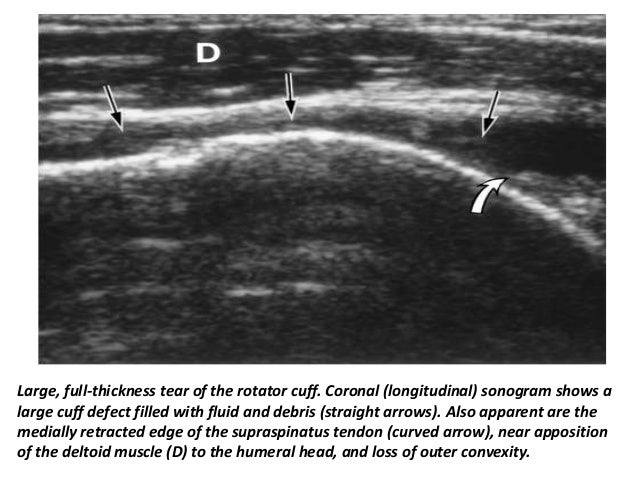

23. 23. Full-thickness cuff tear in a 74-year-old woman. A, The longitudinal image shows that the cuff is retracted medially, and the torn tendon end (T) is surrounded by fluid. B, The transverse image shows the width of the tear (between cursors).

24. 24. Large, full-thickness tear of the rotator cuff. Coronal (longitudinal) sonogram shows a large cuff defect filled with fluid and debris (straight arrows). Also apparent are the medially retracted edge of the supraspinatus tendon (curved arrow), near apposition of the deltoid muscle (D) to the humeral head, and loss of outer convexity.